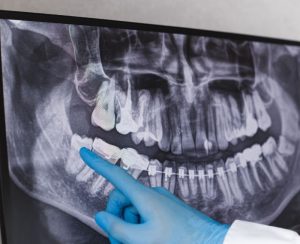

To alleviate the pain associated with wisdom teeth, it is essential to consult with a dental professional, such as those at Happy Smiles Dentist Hornsby, who can assess the situation and recommend appropriate treatment options. Solutions may include over-the-counter pain relievers, prescription medications, or, in some cases, wisdom teeth extraction to prevent further complications and ensure optimal oral health.